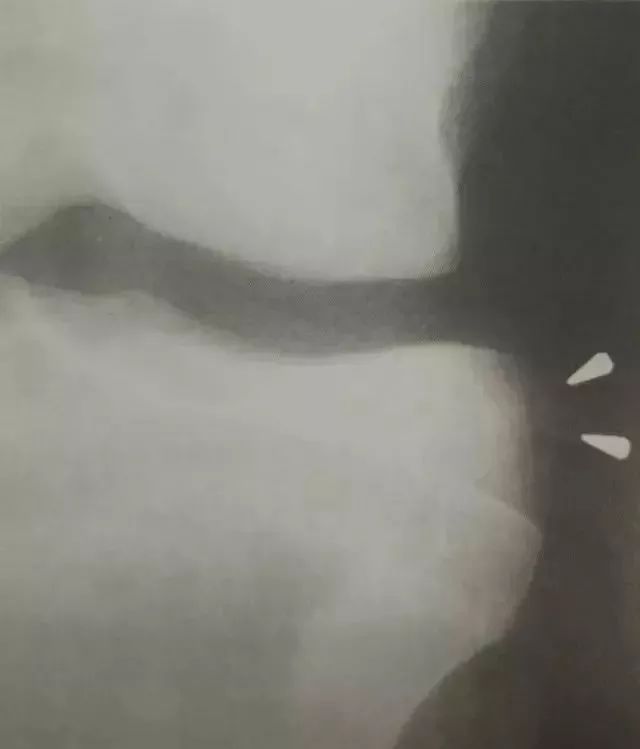

2。外部胶囊符号(Segond骨折)。

对于外部胶囊符号(Segond骨折),请注意从胫骨外侧边缘撕下的小骨块,仅远离关节线,这表明外侧关节胶囊在胫骨的末端撕裂。

(1)在胫骨近端末端的前侧关节和后侧关节末端的抗撕裂性骨折。

(2)建议前交叉韧带撕裂,外侧韧带和关节囊损伤。